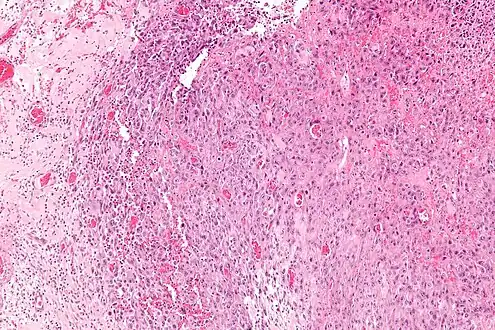

| Micrograph of an epithelioid sarcoma. H&E stain. | |

Histologically, epithelioid sarcoma forms nodules with central necrosis surrounded by bland, polygonal cells with eosinophilic cytoplasm and peripheral spindling.[3] Epithelioid sarcomas typically express vimentin, cytokeratins, epithelial membrane antigen, and CD34, whereas they are usually negative for S100, desmin, and FLI1 (FLI-1).[3] They typically stain positive for CA125.[4]